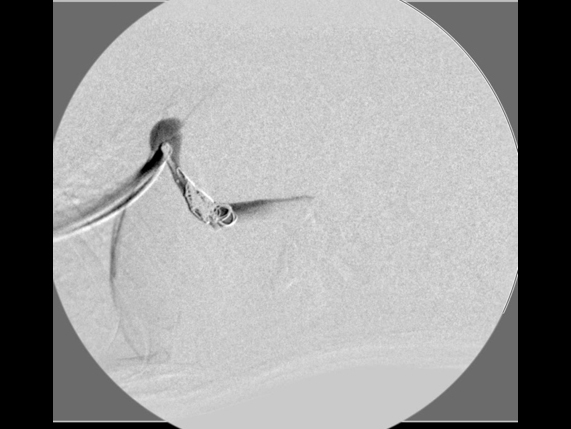

門脈造影検査

コイル設置後の造影検査